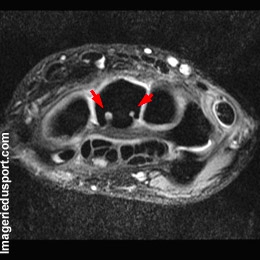

B - IRM coupe axiale, pondération T2 : Interruption corticale nette en regard des formations kystiques (flèches rouges). Ces formations, siègent typiquement en regard de zones d'insertions ligamentaires, en l'occurrence ici, des ligaments palmaires extrinsèques. A noter le net épaississement du tendon de l'extenseur ulnaire du carpe.

Kystes intra-osseux du Capitate.